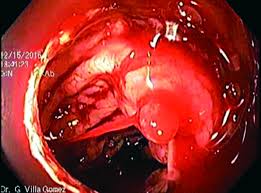

CASO CLÍNICO

Uso de ketamina en el tratamiento del dolor crónico refractario por síndrome de atraimiento del nervio cutáneo anterior con síntomas depresivos asociados.

El síndrome de atrapamiento del nervio cutáneo anterior (ACNES) es una causa subdiagnosticada de dolor abdominal crónico que puede llevar a intervenciones quirúrgicas innecesarias y contribuir al desarrollo de trastornos emocionales como depresión severa e ideación suicida. Este reporte de caso describe a un paciente joven con ACNES y depresión refractaria, tratado exitosamente con infusiones de ketamina en dosis bajas, asociadas a lidocaína, magnesio y analgesia multimodal. Tras seis sesiones, se observó una mejora significativa en la intensidad del dolor, la calidad de vida y los síntomas depresivos.. Leer más |